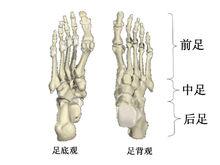

從結構上區分,足部可以分為前足,中足和後足三大部分(圖1),任一部分或關節都非獨立體,而是共同參與足踝部的功能。前足由五列趾骨和與之相連的五根跖骨組成,允許活動,方便行走。中足由五塊不規則的跗骨組成縱弓,起到一定的減震和穩定的作用。而後足由距骨、跟骨和距下關節組成。距骨的上方與小腿兩個長骨(脛骨和腓骨)相連,構成了非單一軸鉸鏈的踝關節。距骨下方與跟骨相連組成距下關節,可允許足部一定的內外翻。跗橫關節又稱為Charcot關節,由距舟、跟骰、舟楔組成的關節,而跖跗關節又稱為Lisfranc關節,是由跖骨基底與骰骨及楔骨相連的關節。踝關節的屈伸運動與距下關節和足的運動是聯合的。當踝關節跖屈時足內翻、內旋,當踝關節背屈時足外翻、外旋。實際上,跖屈背伸運動發生在踝關節。足的內外翻則在距下關節發生,跗橫關節並無真正內外翻作用,僅有側方旋轉。前足內翻外翻時,必伴隨有內旋外旋。

足踝解剖結構及其力學功能圖 1足部骨骼的底背視圖